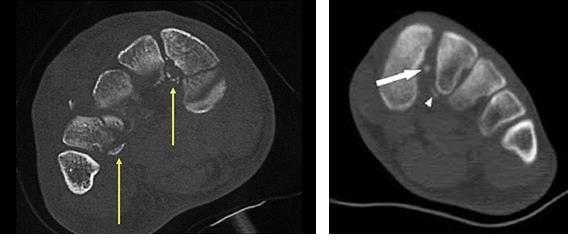

В сложных с диагностической точки зрения случаях целесообразно использование КТ и МРТ.

Отдельно стоит разобрать тему разрыва связки Лисфранка с изолированной нестабильностью 2 предплюсне-плюсневого сустава. Частота данного повреждения значительно выросла за последние 50 лет в связи с популяризацией спорта. Также крайне высота частота отсроченной постановки диагноза. При этой патологии пациента беспокоит боль по тыльной поверхности 1-2-3 предплюсне-плюсневых суставов при физической нагрузке. Часто при осмотре удаётся обнаружить деформацию в данной области. Если осмотр производится отсрочено через несколько недель или месяцев после травмы то клинически определить нестабильность уже не удастся, однако на рентгенограммах с нагрузкой будет виден диастаз между медиальной клиновидной костью и основанием 2 плюсневой кости.

В случаях этого повреждения показано оперативное лечение, открытое устранение подвывиха основания 2 плюсневой кости с фиксацией винтом. Устранение подвывиха производится из доступа в 1 межплюсневом промежутке, рубцовая ткань и остатки связки могут интерпонировать сустав, тогда потребуется их удалить. После вправления производится предварительная фиксация спицей и рентгенологический контроль.

Затем устанавливается винт соединяющий основание 2 плюсневой кости и медиальную клиновидную кость.